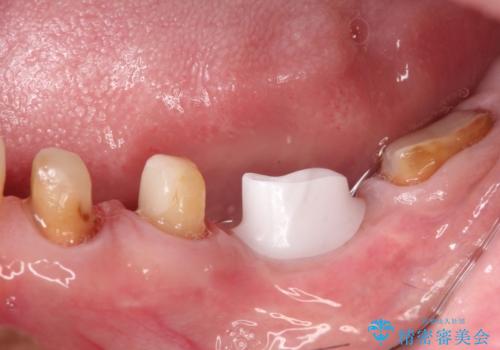

- 左下6番目の歯が欠損しており、インプラントで治療することとなりました。

骨の横幅が薄くなっており、インプラントを埋入するには骨幅が足りない状態でした。

まず最初に骨造成を行い、その後にインプラント埋入手術を行うこととなりました。